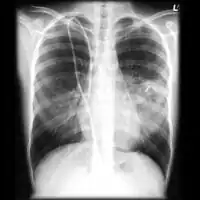

Chest X-ray: Angioinvasive aspergillosis -